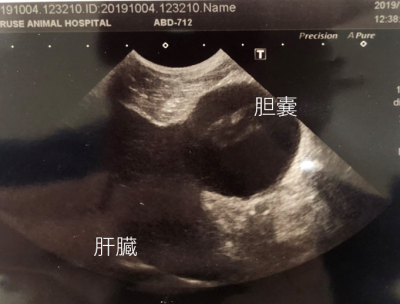

胆汁をためている胆嚢が破裂寸前です。

急いで手術

胆嚢を摘出して

胆汁がでるところの詰まりを流しているところです。

取り出した胆嚢はほとんど機能しない状態になっていて

中身もドロドロのよくない胆汁が入っていました。